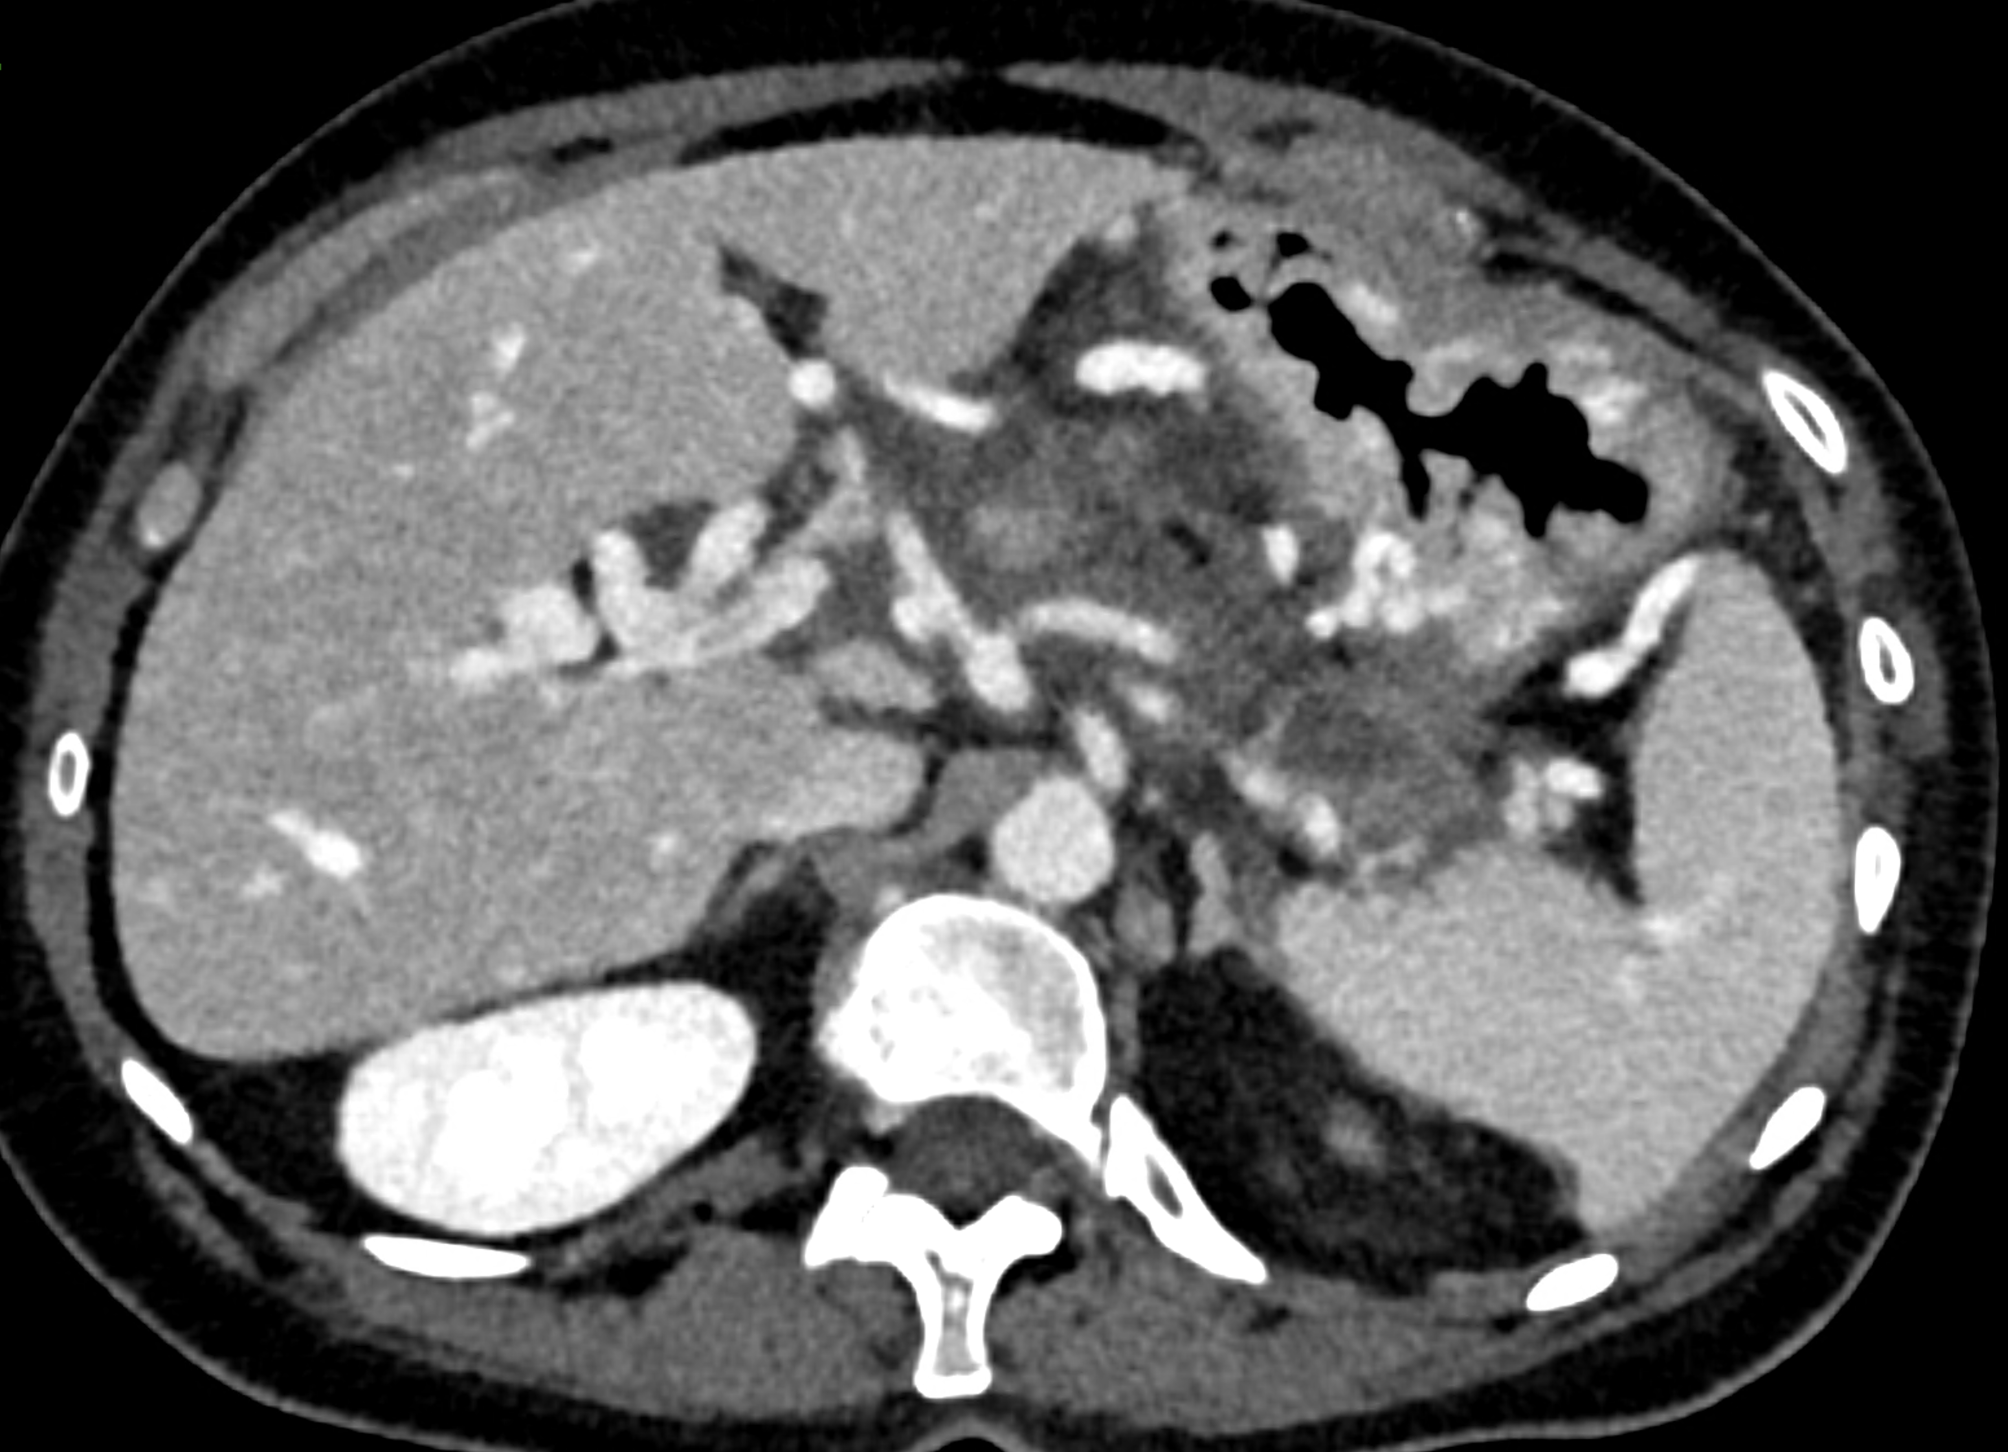

A patient with chronic pancreatitis and chronically occluded portal vein. The bile ducts have a significantly dilated wall, from the trunk, through the stump of the cystic duct, to the right and especially the left branch of the hepatic duct. At the same time, a large pseudocyst in the pancreas, dilatation of the pancreatic duct, and chromic occlusion of the superior mesenteric vein, splenic vein, and portal vein trunk are evident. Along with portal biliopathy, there is also arixy of the cardia and esophagus, as well as cavernous remodeling of the portal circulation itself.

dilated veins in the wall of cystic duct

dilated collaterals in hepatoduodenal ligament partially portal biliopathy, partially cavernous transformation

dilated veins in the wall of common hepatic duct